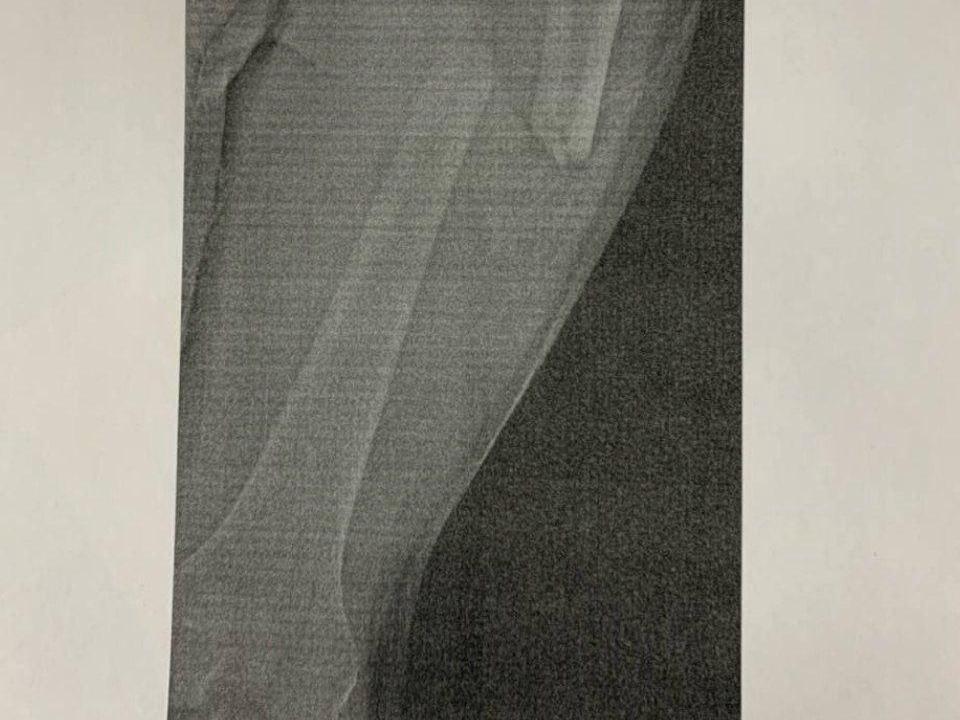

Через несколько месяцев после происшествия пострадавший подробно описал процесс лечения. «Я получил открытый перелом бедренной кости со смещением и слег в „девятку“. Мне сделали три операции, переливание крови, потому что я очень много ее потерял. Мне из коленки доставали гной. Неделю нога висела на вытяжке, потом мне поставили фиксаторы и стержень, доставали осколки. Я лежал в больнице до 22 апреля. До 22 августа ходил на костылях, а потом мне сказали, что у меня кость не срослась», — рассказал парень.